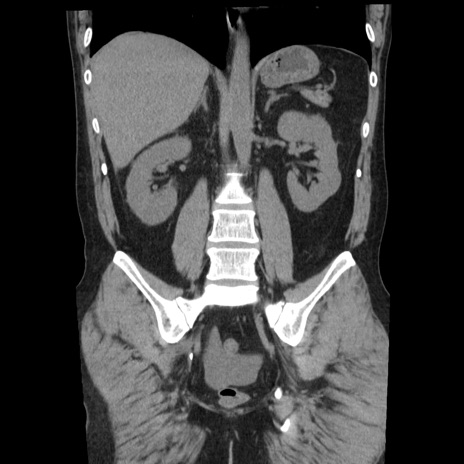

症例29(冠状断像)

【症例】40歳代男性

【現病歴】2日前から胃痛あり。徐々に周期的な激痛に変化した。本日になっても激痛があるため受診。

【身体所見】意識清明、BT 38-39℃台あり、腹部:膨満、やや硬、右下腹部に圧痛あり。

【データ】WBC 8500、CRP 23.26